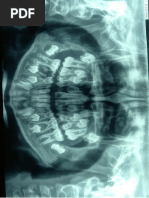

RADIOGRAFA PERIAPICAL #2

(Reabsorcin externa PIEZA 12)

ORIENTACIN DE LA PELCULA RADIOGRFICA

Repujado con la concavidad hacia adelante (vista hacia el paciente) y con

direccion hacia oclusal o incisal

Radiografa periapical perteneciente al cuadrante superior derecho.

NOTACION DENTARIA

La radiografa corresponde al Cuadrante nmero 1, con visibilidad de las

piezas 11, 12, 13.

INTERPRETACION PIEZA 12

La radiografa nos muestra

RAIZ

TERCIO APICAL

No presenta pex, en forma de bisel o meseta

compatible con reabsorcin radicular externa.